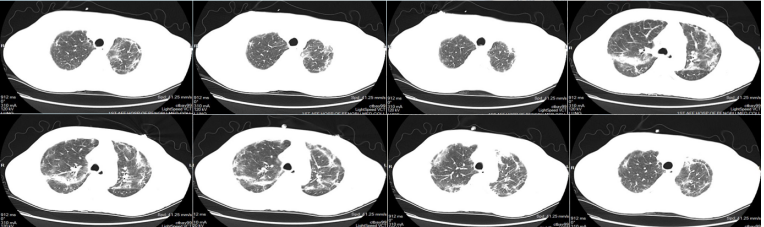

2022年4月25日(D7),患者尿量恢复,撤离CRRT。4月26日(D8),撤机拔管,序贯高流量氧疗。4月27日复查胸部HRCT示:病灶较前明显吸收(图15)4月30日(D12),病情好转出院。嘱托:口服复方磺胺甲噁唑0.96 g q8h维持治疗1年。

15  复查胸部HRCT(2022-04-27)